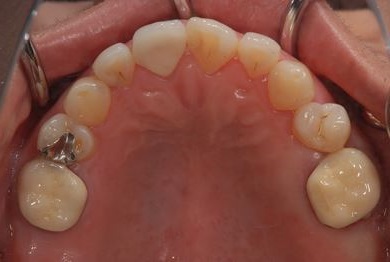

インプラントの症例写真 IMPLANT

インプラント治療+セラミック治療

| 治療内容 | インプラント2本、メタルボンドセラミッククラウン4本、ジルコニアフレームオールセラミッククラウン1本(オールセラミック用土台1本) | ||||||||||||||||||||||||||||||||